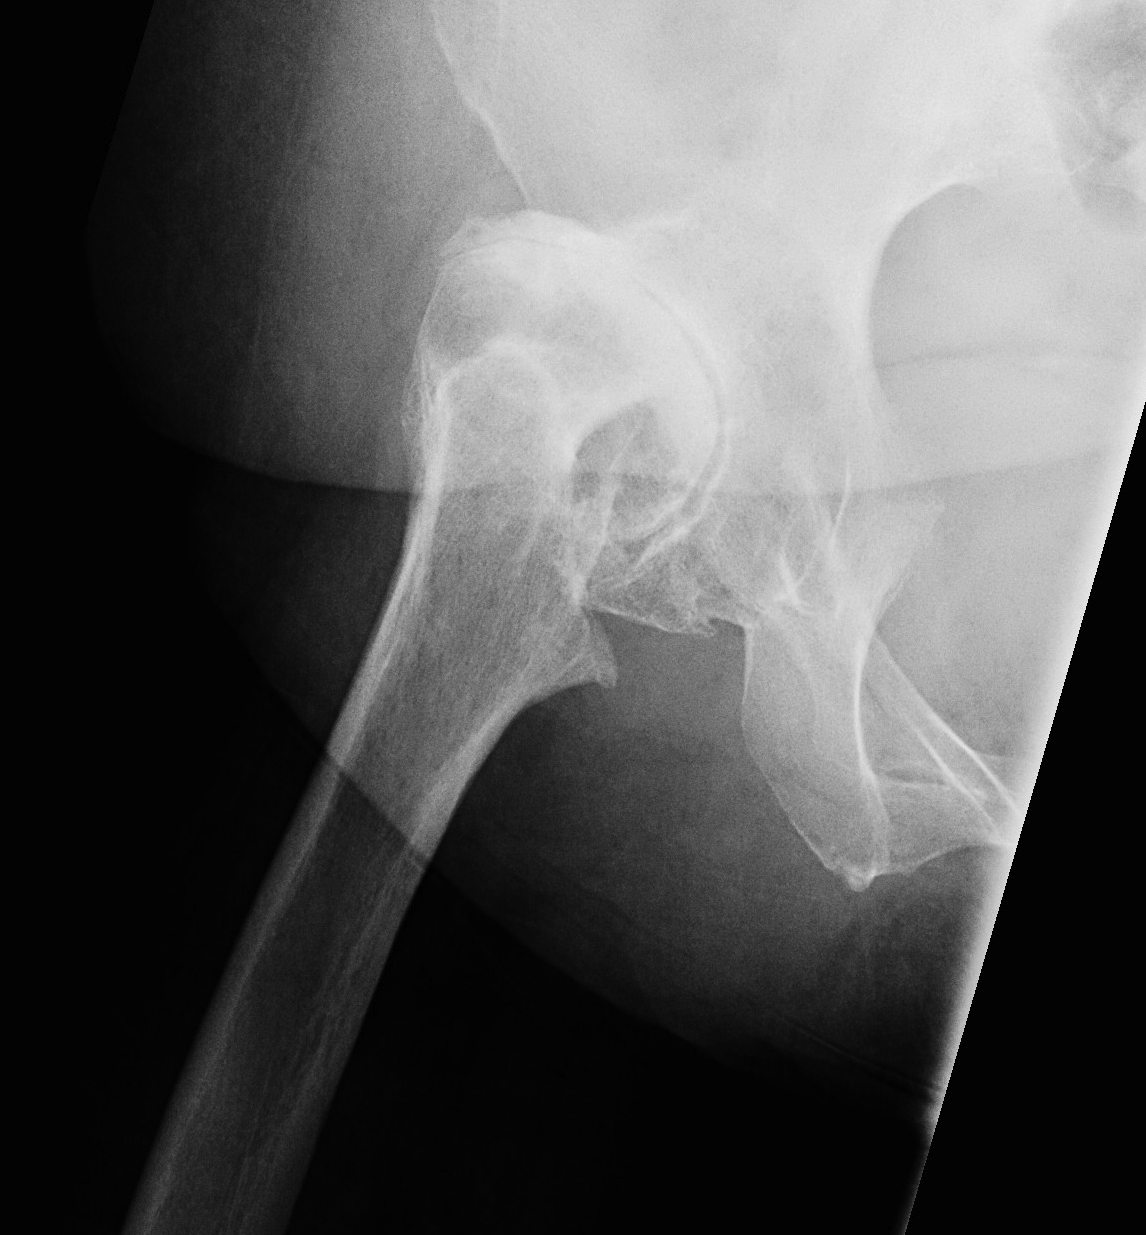

Crowe IV